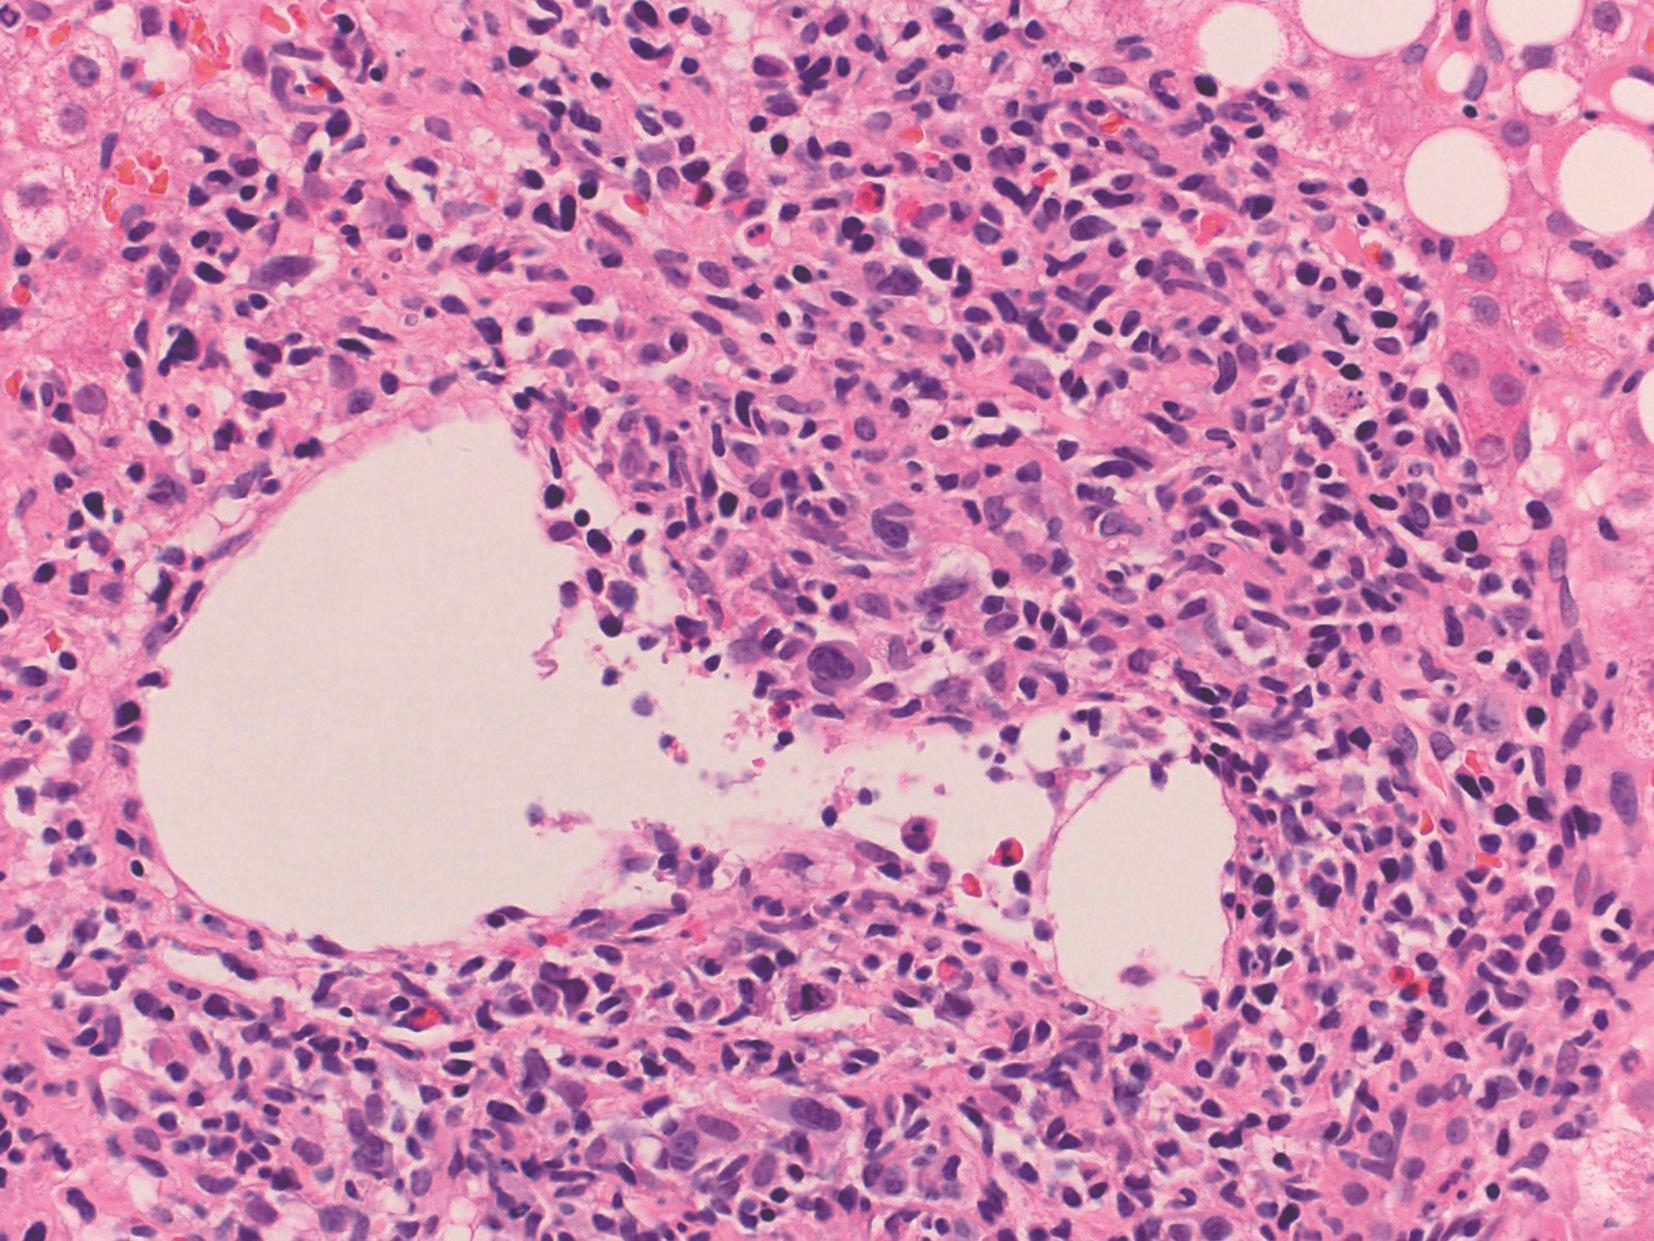

EB病毒为非亲肝病毒、自限性疾病。病理变化为肝小叶炎轻微,肝细胞淤胆不常见,肝窦内单个核细胞呈串珠样排列,汇管区浸润的炎症细胞包括B淋巴细胞、T淋巴细胞和NK细胞,可见异型的淋巴母细胞、静脉内皮炎,可伴肝细胞脂肪变、肉芽肿和胆管系统损伤(图4-18-1)。EB病毒编码的小RNA(EBER)原位杂交证实病毒(图4-18-2)。

图4-18-1 EB病毒性肝炎